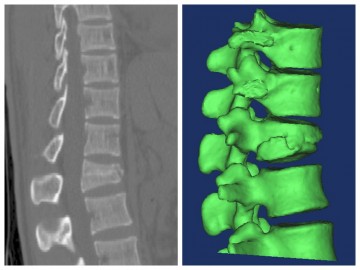

南医五院成功开展经皮椎弓根螺钉内固定技术微创治疗胸腰椎骨折

发布时间:2016-06-08 14:50:15

胸腰椎骨折是临床常见的一种脊柱创伤,临床表现以腰部疼痛伴活动受限为主,手术治疗恢复胸腰椎稳定性及正常生理曲线已成为目前最主要治疗选择,能明显降低椎管狭窄、神经损伤等并发症的发生率。手术治疗有传统开放手术与新型微创手术两种方案,相对于开放手术,微创手术具有创伤小、恢复快等优点,得到广泛临床应用与推广。 ...